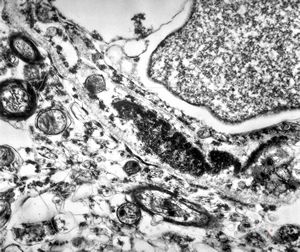

F,50y. | progressive multifocal leukoencephalopathy- viral particles in a glial cell

F,50y. | progressive multifocal leukoencephalopathy- viral particles in a glial cell

F,50y. | progressive multifocal leukoencephalopathy- viral particles in a glial cell